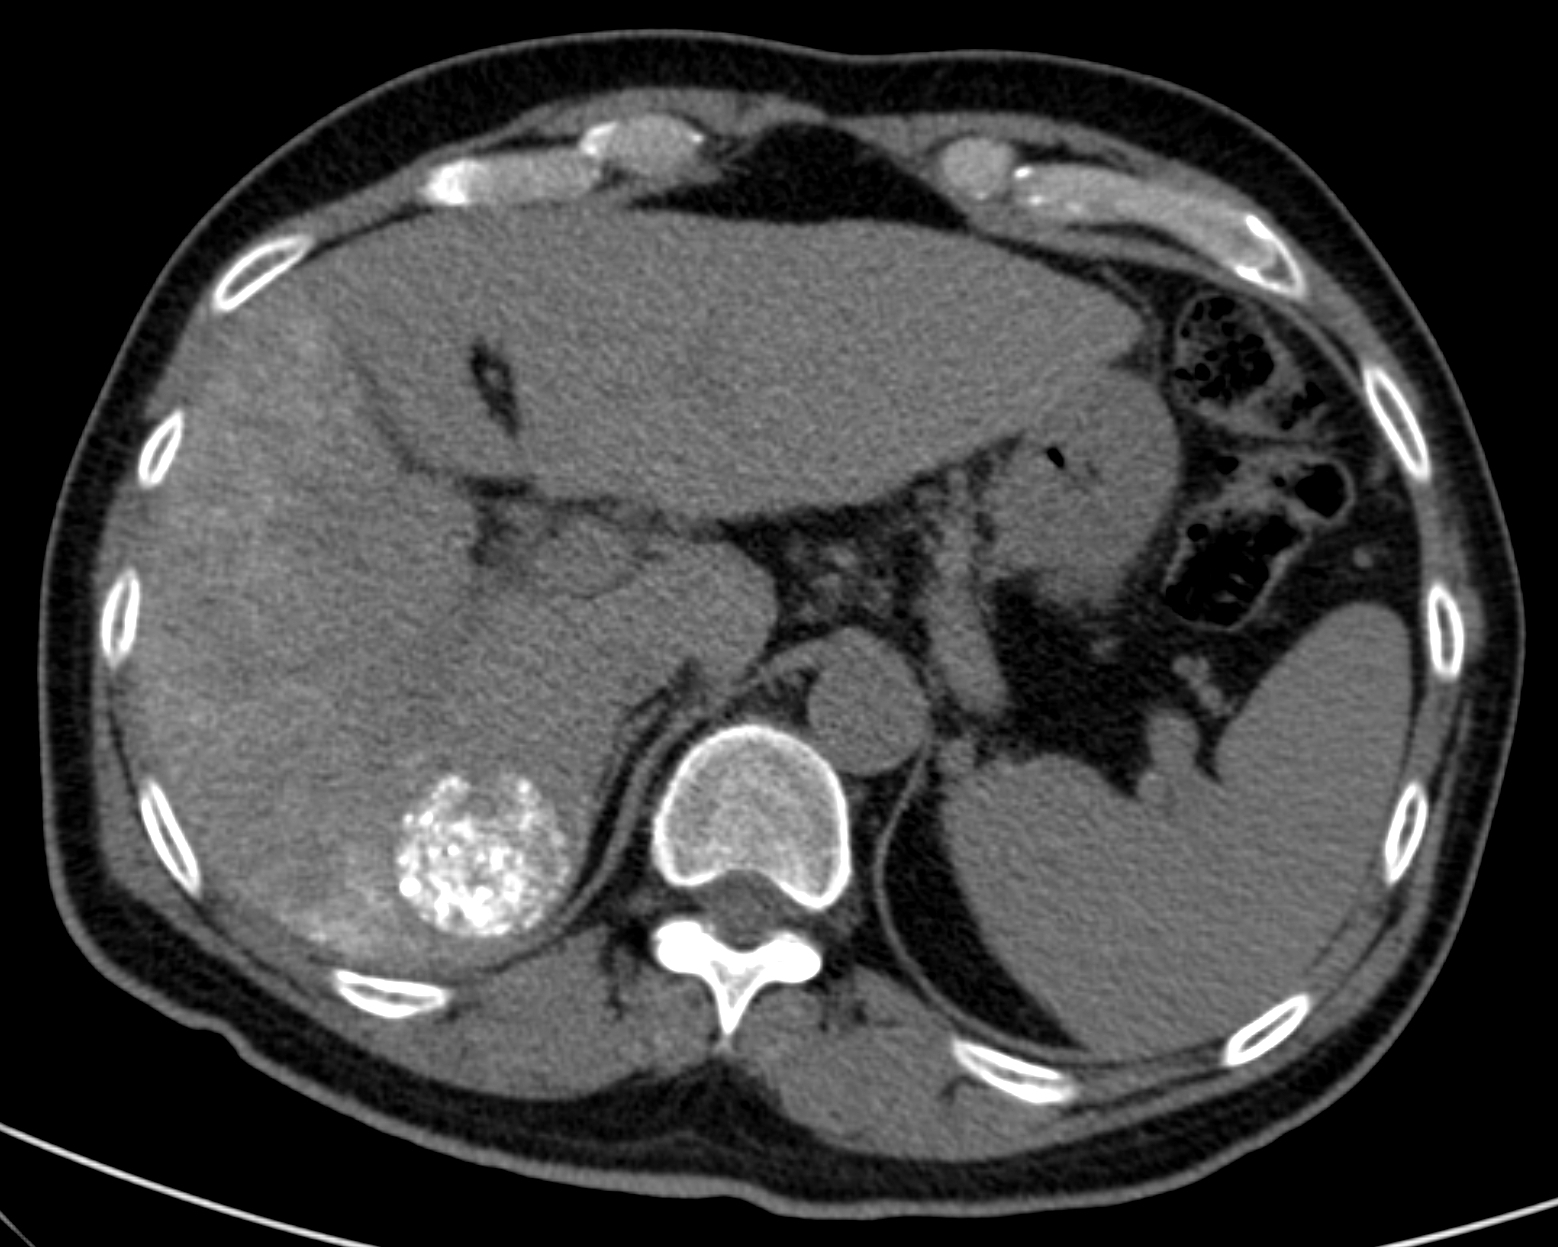

Very variable appearence forms can be observed by US and CT examinations from the early cyst in active phase to the cyst of the died parasite with a calcified wall (although the calcium appearing in the wall of the cyst does not mean that the parasite has unambiguously consumed) in case of an E. granulosus infection (Figure 15).

Figure 15: Echinococcus cyst in the liver, contrast enhanced CT

On the other hand, the liver parenchyma affected by E. multilocularis appears as areas with irregular contour and mixed echogenecity (US) or density (CT) including a hypoechoic (US) or hypodens (CT, this is already the necrotic area) necrotic center (multilocular cyst with inner matrix).